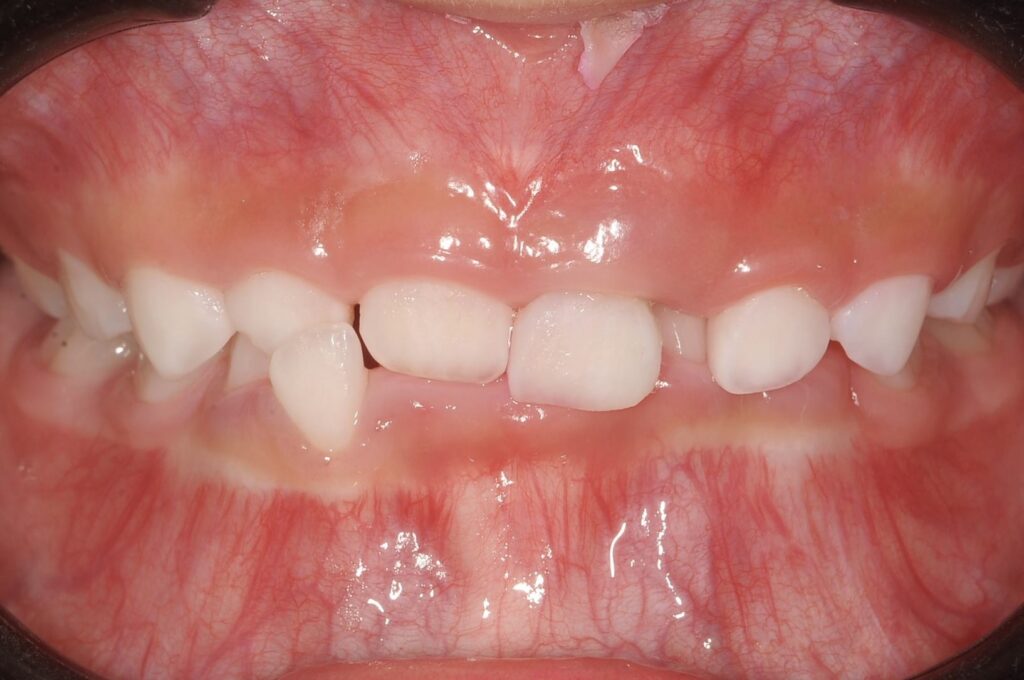

5歳 女児 小児矯正

歯並びの状態:

叢生(ガタガタ)

過蓋咬合(咬み合わせが深い)

BEFORE

主訴

右下の歯が飛び出ているので治したい。

診断名・主な症状

過蓋咬合

年齢

5歳

治療内容

上下の歯並びの幅を拡げつつ、前歯の関係を改善しました。